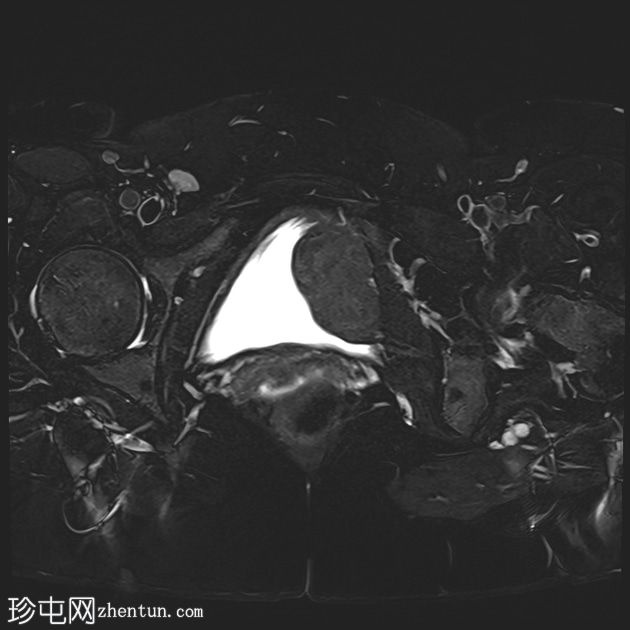

轴位T2加权像

脂肪抑制像

可见膀胱左侧壁有一边界清晰的T2低信号实

性病

灶,无扩散受限,均匀强化。未见膀胱周围侵犯或肾积水。

子宫底部前壁可见一小肌瘤。双侧卵巢可见无强化囊肿。盆腔及腹股沟未见异常淋巴结肿大。

这是一例经组织学证实的膀胱平滑肌瘤病例。